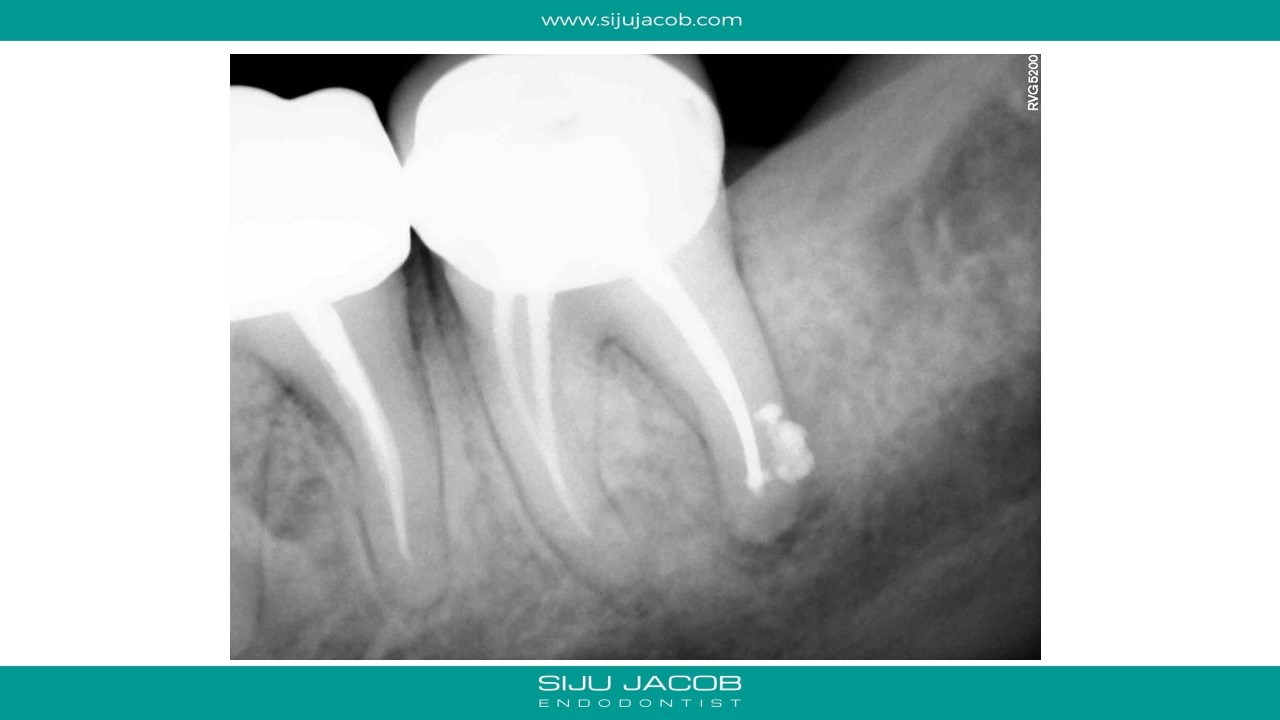

Selective Re-treatment of Distal Root

Patient came in with a sinus tract and lesion in the distal root. I Re-treated just the distal root alone. sinus tract disappeared after 2 weeks of Caoh.